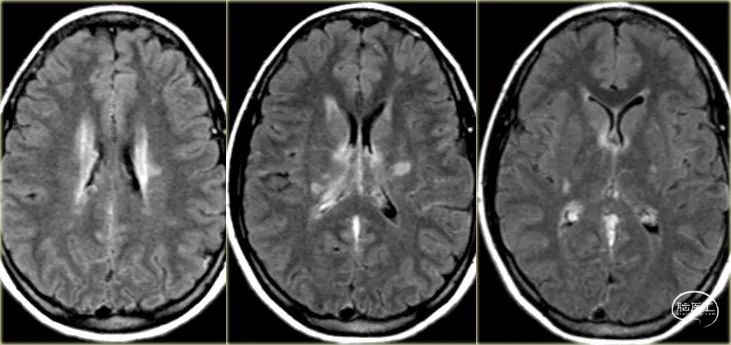

下图 有血管源性水肿(红色箭头),细胞毒性水肿和出血(蓝色箭头)。

这些发现和位于颞叶的位置,应该会让你想到由Labbe静脉血栓所致的静脉梗塞。下一次检查应该是增强的MR或CT,以证明诊断。